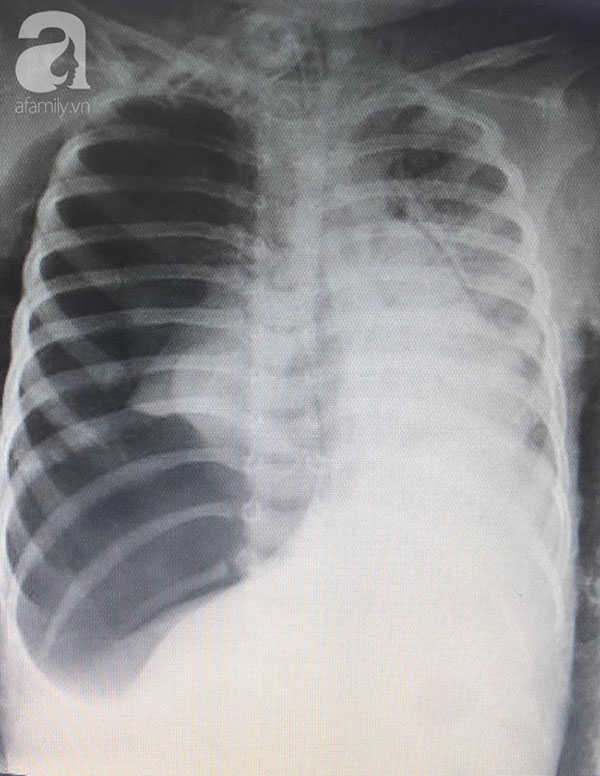

Khi đến BV Nhi đồng Thành phố (TP.HCM), bé đã ngưng tim ngưng thở trước đó, tổng trạng xấu, da bông tím, tràn khí màng phổi, sốc nặng nề...

Bệnh nhi nhanh chóng được thở máy thông số cao, chọc hút khí màng phổi, ổn định hô hấp, huyết động, dùng thuốc vận mạch. Tiến hành hội chẩn và chụp X-quang, ekip nội soi khi nghi ngờ có dị vật đường thở và cha mẹ bé cũng cho rằng con hóc hạt đậu phộng.

Khẩn trương tiến hành nội soi, đi sâu vào vào đường mũi bằng ống soi mềm, ekip nội soi bất ngờ khi thấy dị vật chèn sát ngay phế quản gốc bên phải.

Sau điều trị tích cực, tình trạng tràn khí màng phổi của bệnh nhi cải thiện rõ, áp lực phổi, thông số máy thở hỗ trợ giảm đáng ghi nhận, bé đáp ứng kháng sinh điều trị viêm phổi tốt. Đến nay sau hơn nửa tháng hồi sức tích cực, các bác sĩ đã rút ống thở cho bé.